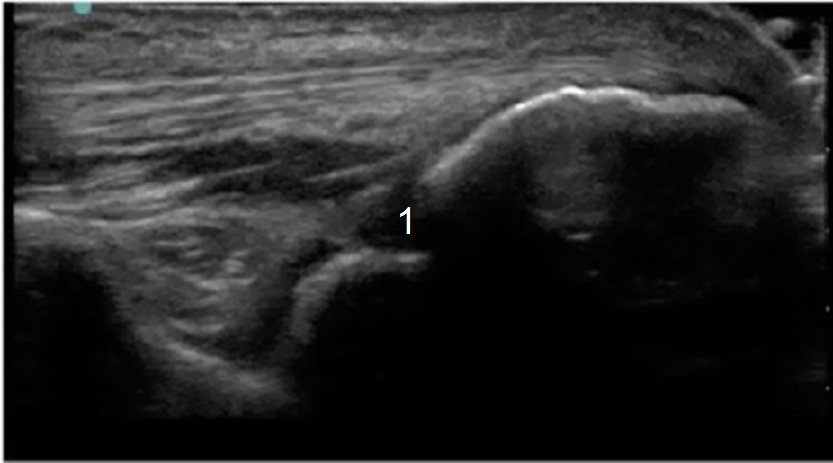

肘関節内注射後陥凹針のターゲットの画像

針のターゲット